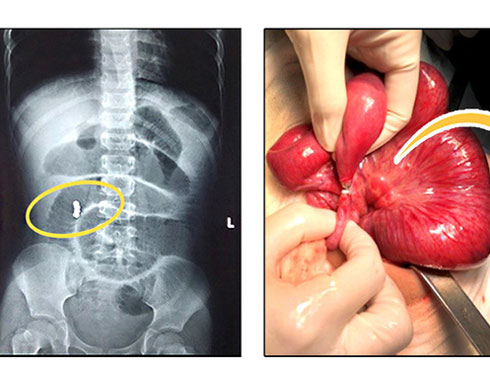

Sau khi tiếp nhận, các bác sĩ tiến hành làm các xét nghiệm và chụp xquang ổ bụng bệnh nhi. Kết quả chụp X-quang phát hiện hình ảnh tắc ruột do dị vật hình tròn, bao gồm nhiều viên nhỏ và dính thành chuỗi. Ngay lập tức, các bác sĩ khoa Ngoại và khoa GMHS đã tiến hành hội chẩn và chỉ định mổ cấp cứu.

25 viên bi nam châm trong ổ bụng